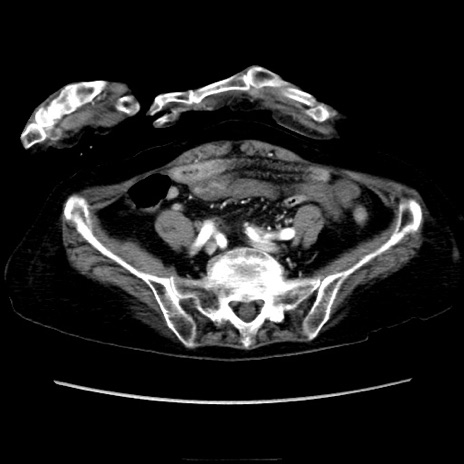

症例40(横断像)

【症例】90歳代女性

【主訴】腹痛・嘔吐

【現病歴】 食欲低下、嘔吐があり昨日他院受診。肺炎と診断され入院となる。入院後より腹部全体に圧痛あり。胃管留置され経過みていたが、症状持続するため、

当院転院となる。

【既往歴】胸椎圧迫骨折、胆石症

【身体所見】腹部:中央に激痛あり、圧痛あり、反跳痛不明

【データ】WBC 17100、CRP 18.82

横断像